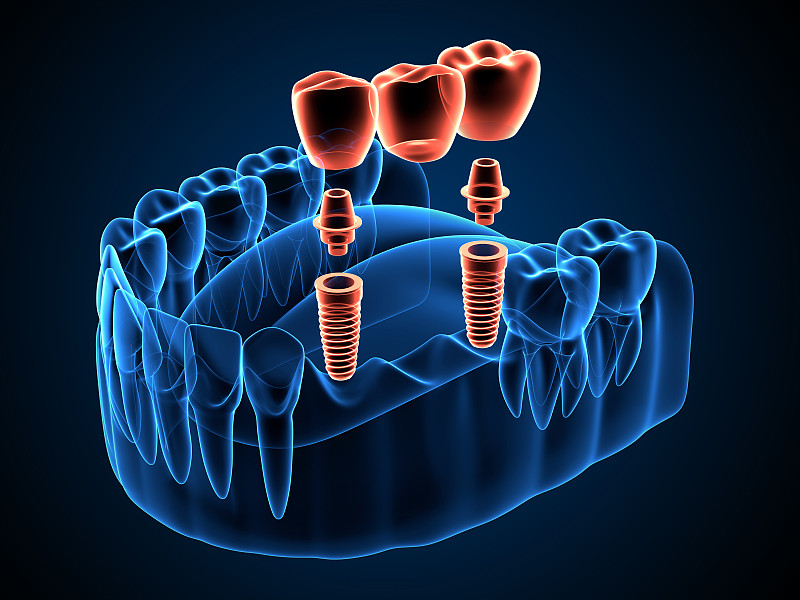

种植局部义齿3d渲染详情

JPG